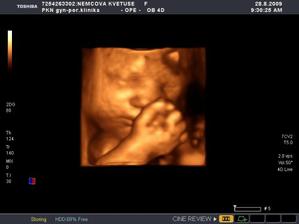

Nová naděje. Bohužel to bylo opět stejné, jako již dvakrát předtím. Třetí revize, třetí ztráta naděje. Jsem po laparoskopii a hysteroskopii a čekáme na výsledky imunologie v Plzni. Pak se uvidí co dál. V únoru 2009 nám v Sanusu doporučili ještě dva měsíce domácího snažení. Tak jsme se snažili a nyní napjatě sledujeme čárku. HCG nám krásně stoupá, 20. den po ovulaci je 2066. Máme 1. fotku dutinky. Přes nejrůznější potíže a patnáctidenní hospitalizaci nám miminko krásně roste. 22. dubna konečně po čtrnácti dnech ukázalo nosánek, máme nosní kůstku, NT je 2,0. Máme vše, co máme mít a rodiče se dnes poprvé společně dívali na ultrazvuk. Viděli mě i 4D, to koukali. Odnesli si video a teď na něj pořád koukají. Další kontrola náš čeká 5. května, opět ultrazvuk, triple testy a poradna. Trošku změna situace, mamka se mnou leží od 27. dubna v nemocnici, ale já ji dělám radost, rostu, 16.6. už vážím 360 gramů a od 5.6. ji kopu a ona o tom ví. Od 10. 6. se nám začal malinko měnit nález až jsme museli 10. 7., gr. h. 24+2 na cerclage, potom jsme měli zánět ledvin a astmatický záchvat. Pořád mamce tvrdlo břicho, tak se bez infuzí neobejde. 18. 7. se ještě objevilo krvácení, ale nebylo to nic závažného, byli jsme na ultrazvuku a vážím 908 gramů. V pátek 24.7. se to zlepšilo a kapeme na nejnižší rychlost, hurá. Mamka zatím nesmí chodit, má to slíbeno na 2. září. Kapeme sice na nejvyšší rychlosti, ale na ultrazvuku 4.8. mám odhad 1280 gramů. Dne 18.8. jsme byli na ultrazvuku a mám odhad 1750 gramů, mám trochu víc plodové vody a tak si tam plavu jako v bazénku. Dne 28.8. jsme byli s mamkou zase na ultrazvuku, vážím už 1950 gramů, mám udělaný krásný 3D fotečky, vody už nemám tolik moc, tak je mamka ráda. Jen se nám zase zkrátil čípek, už mě tam drží jen steh a 13 mm, ale držím mamce pěstičky, aby jsme vydrželi. No a taky si musím zvykat, mamka totiž má už dovoleno chodit na wc, a já jsem byl zvyklej, že pořád leží. Je sice z toho unavená, ale šťastná. Já jsem jí ještě udělal radost, že jsem se přetočil hlavičkou dolů. Dne 1.9. se mi konečně podařilo zbavit se té nitě, co tam mamka měla. Všichni jsou překvapení, jak se to mohlo stát, ale steh je pryč. Dne 10. 9. jsme s mamkou byli zase na ultrazvuku, vážím 2368 gramů (33+1). Hrdlo máme sice jen 9 mm, ale já se tam ještě udržím! Plodové vody mám už akorát, mamce klesly jaterní testy, žlučové kyseliny jsou v normě, tak má radost. Tak dnes 17. 9. jsem se byl zase vážit, mám 2517 gramů. Hrdlo má mamka jen 6,7 mm s obrovitým funnelingem, ale pořád drží. Denně mi točí monitory, mám je vzorné a pořád nemůžu přijít na to, jak ty sondy odkopnout. 26.9. pustil pan doktor mamku na propustku, byla poprvé 12 hodin mimo nemocnici, byli jsme na zahradě, grilovali jsme a já jsem babičce, dědečkovi a strejdovi předváděl, jak umím krásně kopat. Mamka byla moc šťastná. Večer se vrátila do nemocnice, dala si po 23. hodině sprchu a když usínala, tak jsem ji hodně překvapil, vypustil jsem svůj bazén. A tak se nešlo spinkat, ale na porodní sál. Šlo to pěkně a přesně ve 4.00 hodin jsem se narodil za skvělé asistence mého tatínka, který mamince na sále moc pomáhal. Vážím 2740 gramů a měřím 50 cm. Dosáhl jsem gestačního stáří 35+4. Rodiče a velká spousta lidí kolem ze mě mají velikánskou radost. Trošku jsem odmítal v inkubátoru dýchat, tak mě 1 den pomáhal CPAP. Večer mi ho vzali a teď už se snažím sám. mamka za mnou chodí a já jsem rád, když ji vídím. Dnes jsem na ni poprvé otevřel očička, snažím se papat, dnes už ze stříkačky. Tatínek je ze mě unešenej a já jsem rád, když mě přijde pohladit a vyfotit.